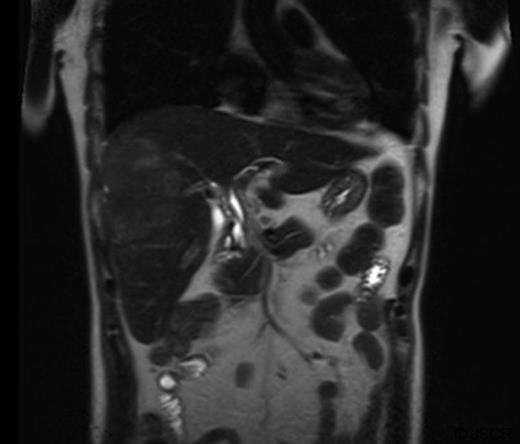

The mass had mild hyperintense signal on T2-weighted images and capsule retraction, suggesting a scirrhous lesion (figure 3); possibly cholangiocarcinoma.

T2 weighted abdominal MRI, coronal view displaying right lobe liver mass.